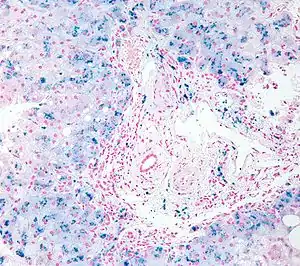

Micrograph of liver biopsy showing iron deposits due to haemosiderosis. Iron stain.

Selective iron deposition (blue) in pancreatic islet beta cells(red).